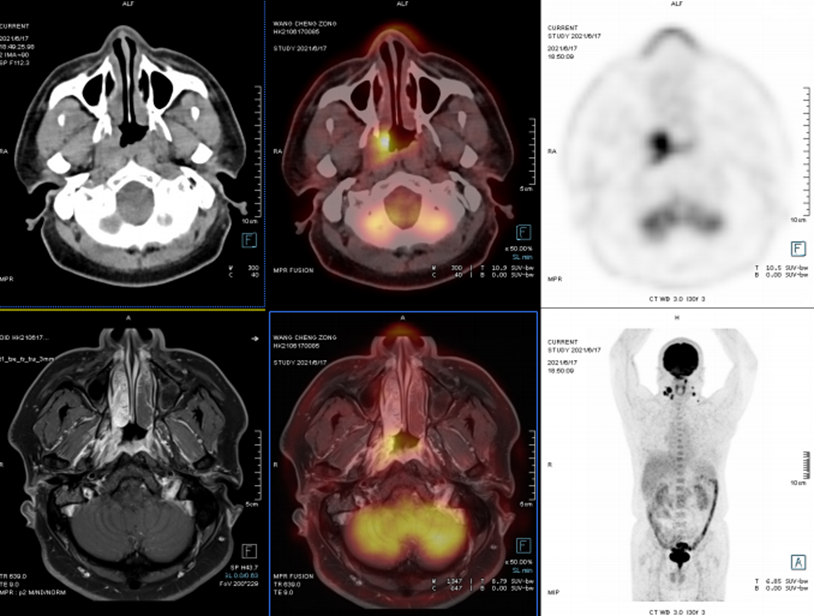

头颈部

案例:鼻涕带血半年余,2021-6-8喉镜:咽鼓管开口处新生物。为进一步明确诊断,行PET/CT-MR异机融合检查。

表现:右侧鼻咽壁不规则软组织增厚,FDG摄取增高,结合外院病理,符合鼻咽癌表现。两侧颈深上、中间隙及两侧咽旁间隙多发淋巴结转移。

病理:右鼻咽部非角化型分化性癌